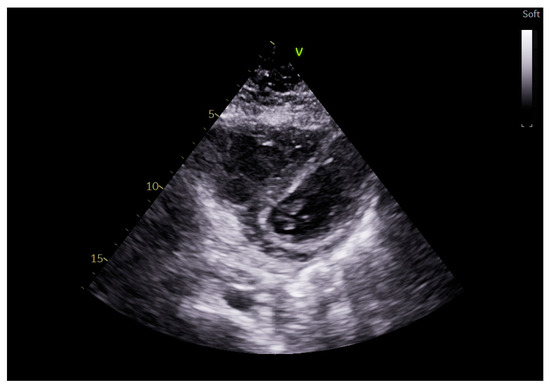

5. Right Ventricular Echocardiographic Evaluation

3. Heart–Lung Interaction in Mechanical Ventilation

4. Echocardiographic Evaluation in Mechanical Ventilation